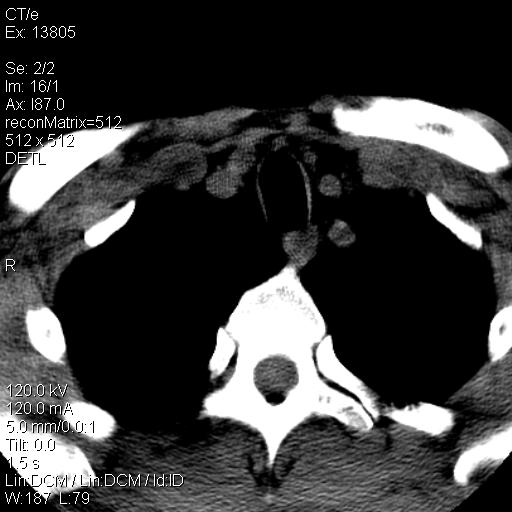

上腹部疼痛一月,呕吐10天,发现左侧颈部包快10天 胸部cr片未见明显异常。

腹膜后淋巴结增大,转移、淋巴瘤?胰腺增大,胰腺炎?占位?颈部考虑增大淋巴结。建议腹部增强扫描。

颈部及腹膜后淋巴瘤可能性大